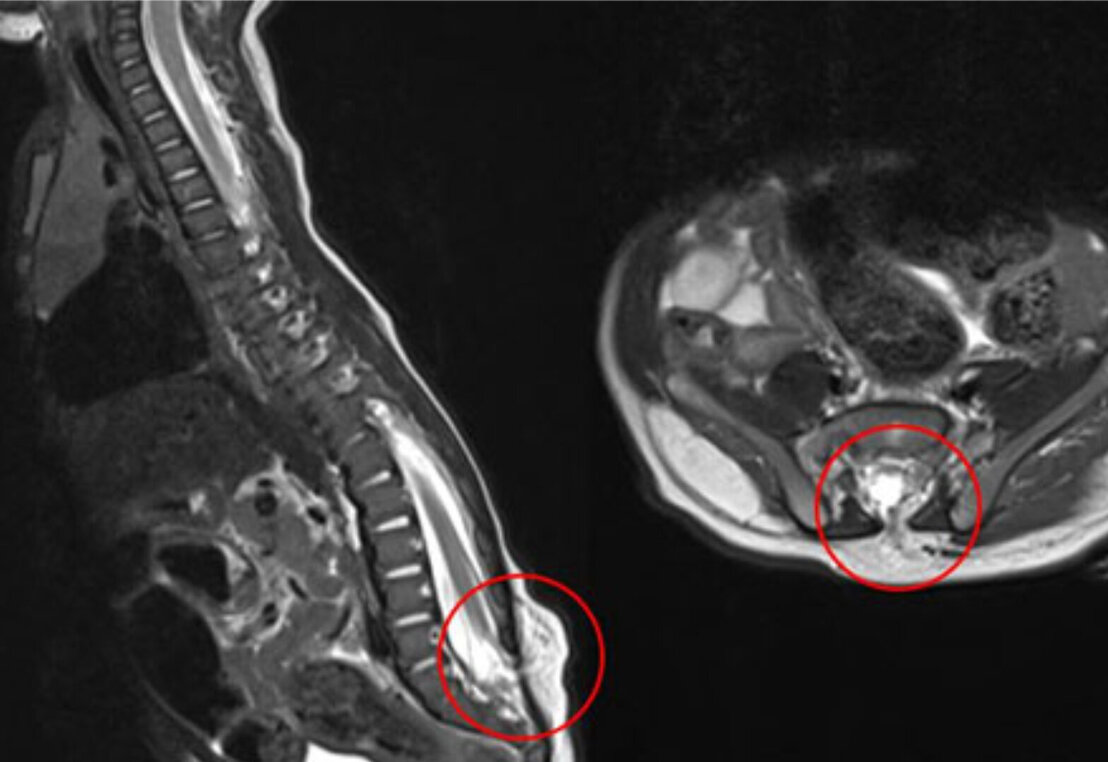

Bei dieser Form der Fehlbildung ist die Spaltbildung in der knöchernen Wirbelsäule geschlossen, also von intakter Haut bedeckt. Typische Befunde, die den Verdacht auf eine Spina bifida occulta erbringen sind atypische Behaarungsmuster oder Pigmentstörungen der Haut über der Fehlbildung. Sind zusätzlich Fehlbildungen des Rückenmarks oder seiner Häute vorhanden (z.B. Tethered Cord, Split Cord Malformation, Spinales Lipom oder Dermalsinus) kann es zu neurologischen Ausfällen kommen und eine operative Therapie indiziert sein.

Bei dieser Form der Fehlbildung ist der Defekt offen und es kommt zu einer Ausstülpung der Rückenmarkshaut (Meningocele) oder von Rückenmarkshaut und Anteilen des Rückenmarks (Meningomyelocele) nach außen. Die neurologischen Ausfallserscheinungen sind abhängig von der Ausprägung und Höhe des Defektes. Häufig liegt auch eine Kombination mit anderen Fehlbildungen wie der Chiari-Malformation vor. Wegen der hohen Infektionsgefahr und den entsprechenden gravierenden Folgen ist eine rasche operative Deckung dieses Defektes nach der Geburt die Therapie der Wahl.